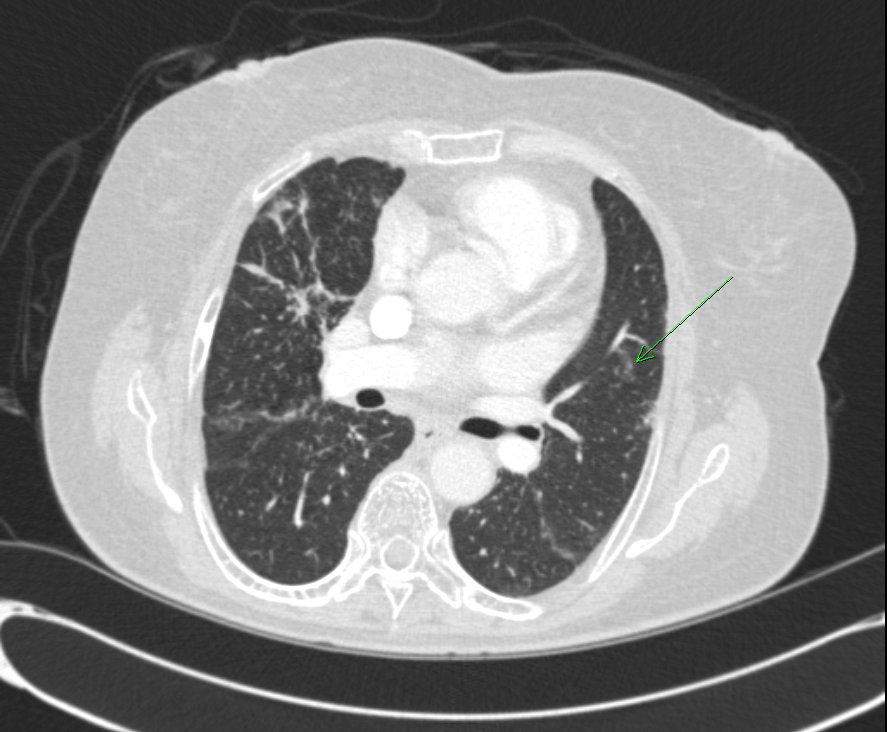

* CXR °ú  chest CT  »çÁøÀÔ´Ï´Ù.

¶Ñ·ÇÇÑ ¿µ»óÀ» À§ÇØ f/u Áß¿¡ ÂïÀº »çÁøÀ» ÷ºÎÇÏ¿´½À´Ï´Ù.

l  Chest CT

Progression of multiple small nodules in both lungs, along peri-BV and ILS, dominant on RUL and RML. No significant change of several small LNs in both hilar and mediastinum.   COPD: diffuse bronchitis. LH enlarge and PAH.